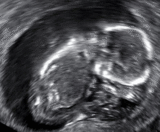

| An ultrasound showing an empty sac, a gestational sac containing a yolk sac but no embryo. This is a type of miscarriage. | |

An anembryonic pregnancy (also called an "empty sac" or "blighted ovum") is a condition where the gestational sac develops normally, while the embryonic part of the pregnancy is either absent or stops growing very early. This accounts for approximately half of miscarriages. All other miscarriages are classified as embryonic miscarriages, meaning that there is an embryo present in the gestational sac. Half of embryonic miscarriages have aneuploidy (an abnormal number of chromosomes).[20]